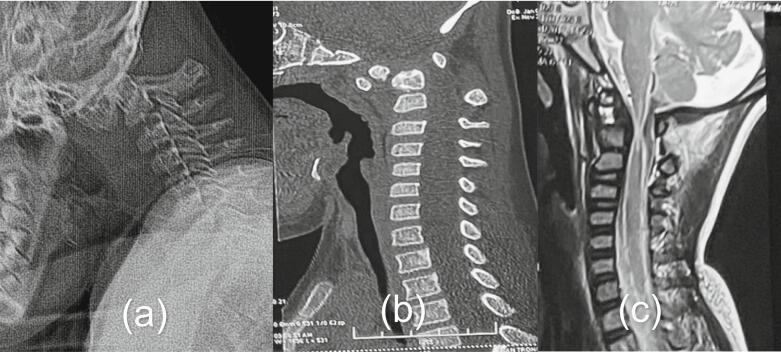

We present two cases of Os odontoideum accompanied by Down syndrome. Both patients were hospitalized due to progressive tetraparesis after falls several months prior. Upon examination, the patients exhibited myelopathy and were unable to walk or stand. MRI revealed spinal stenosis at the C1-C2 level due to atlantoaxial dislocation. C1-C2 fixation using Harms' technique was performed in both cases. One case experienced a complication involving instrument failure, necessitating revision surgery.

我们报告两例伴有唐氏综合征的齿突缺如病例。两名患者均因数月前跌倒后进行性四肢轻瘫入院。检查时,患者表现出脊髓病,无法行走或站立。MRI显示由于寰枢椎脱位,C1-C2水平存在椎管狭窄。两例均采用哈姆斯(Harms)技术进行C1-C2固定。其中一例出现器械故障并发症,需要进行翻修手术。